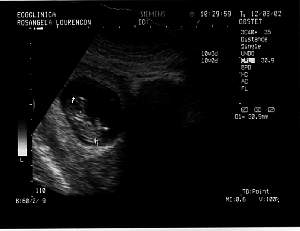

2nd Session - 9th April 2002

Week: 14

Size: Around

8 cm

Obs: Mother and baby fine

The dude is scratching his

head

Flexing the legs to become

a great biker